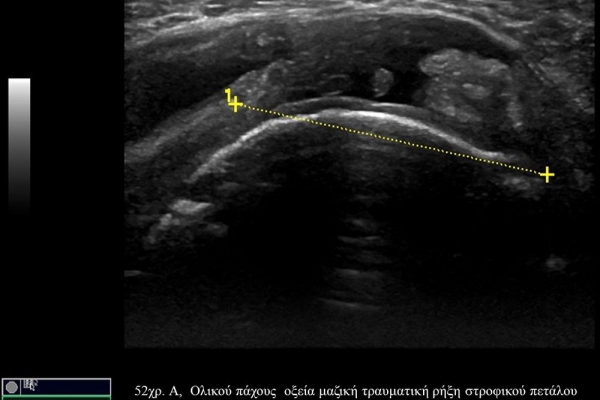

Πρόκειται για υπερηχογράφημα υψηλής ευκρίνειας που επιτρέπει την λεπτομερέστατη απεικόνιση (σε επίπεδο χιλιοστού) ακόμη και πολύ μικρών/επιφανειακών ανατομικών δομών και απαιτεί ειδικό υπερηχογραφικό εξοπλισμό καθώς και εξειδίκευση του ακτινολόγου. Η εξέταση γίνεται με δυναμικό τρόπο, δηλ εκτελούνται δοκιμασίες κίνησης του μέλους που πάσχει, ώστε να αποκαλυφθεί η παθολογίαακόμη και όταν δεν είναι εμφανής σε θέση ηρεμίας. Επιπλέον, η εξέταση είναι ανώδυνη και ασφαλής και δεν περιλαμβάνει ακτινοβολία (CT), μαγνητικό πεδίο (MRI) ή παραμονή σε κλειστό χώρο και είναι πολύ ανεκτή τόσο σε ενήλικες όσο και σε παιδιά.

- Παθήσεις Ώμου (πχ ρήξη στροφικού πετάλου)